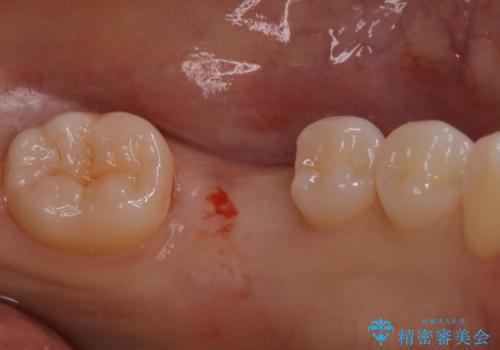

- 他院で抜歯と言われ、今後どうしたらいいのかを相談された患者様です。

抜歯を行った後は、Br、義歯、インプラント、何もしないという選択肢のメリットデメリットを説明させていただき患者様がインプラント治療を希望されたので今回治療させていただくことになりました。

歯のなかったところをインプラント治療を行うことによってまた噛める喜びを感じていただけて良かったと思っております。